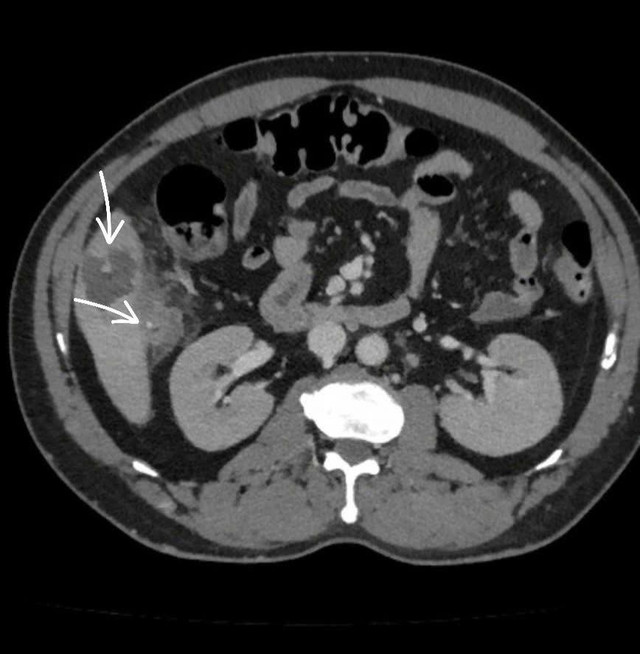

Kết quả chẩn đoán hình ảnh (CT scan) cho thấy một mảnh xương nhỏ xuyên qua thành đại tràng tại góc gan, găm vào nhu mô gan hạ phân thùy V, tạo ổ áp xe kích thước 56x36mm, kèm viêm dày thành đại tràng vùng góc gan. Đây là nguyên nhân chính gây ra ổ nhiễm trùng nguy hiểm.